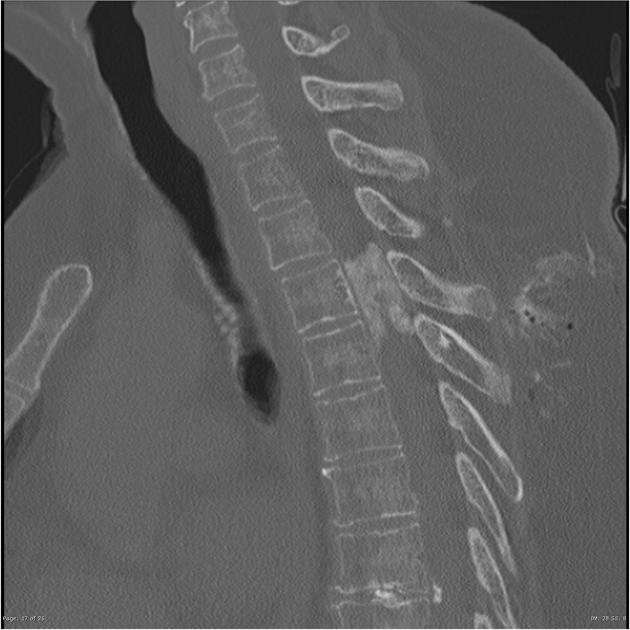

位于硬膜內(nèi)的脊柱腫瘤發(fā)病率為每年每10萬(wàn)人3 ~ 10例,其中硬膜內(nèi)髓外腫瘤占椎管內(nèi)腫瘤的2/3,其中脊髓腦膜瘤占脊髓腫瘤的25-46%。它們由與神經(jīng)嵴細(xì)胞不...